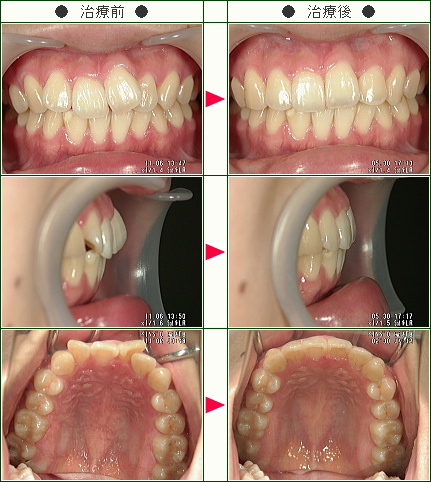

☆歯のデコボコ矯正症例[T.H様 19歳 男性]

「主訴」前歯のデコボコ

「治療方法」マウスピース矯正

「治療期間」マウスピース矯正6か月

「費用」33万円

「治療等の主なリスク、副作用」

部分矯正治療では前歯を中に入れる際には歯の隣接面を削るIPRが必要です。